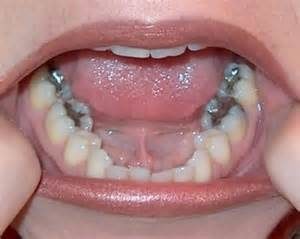

Amalgam fillings were the most common, cheapest filling available. However, amalgam fillings contain mercury and are not commonly used in Australia. Moreover, this type of filling can expand and contract in heat which can cause teeth to crack. For this reason, we do not offer amalgam fillings at Coastal Dental Care. Instead, we offer to replace old amalgam fillings with healthier tooth coloured fillings.